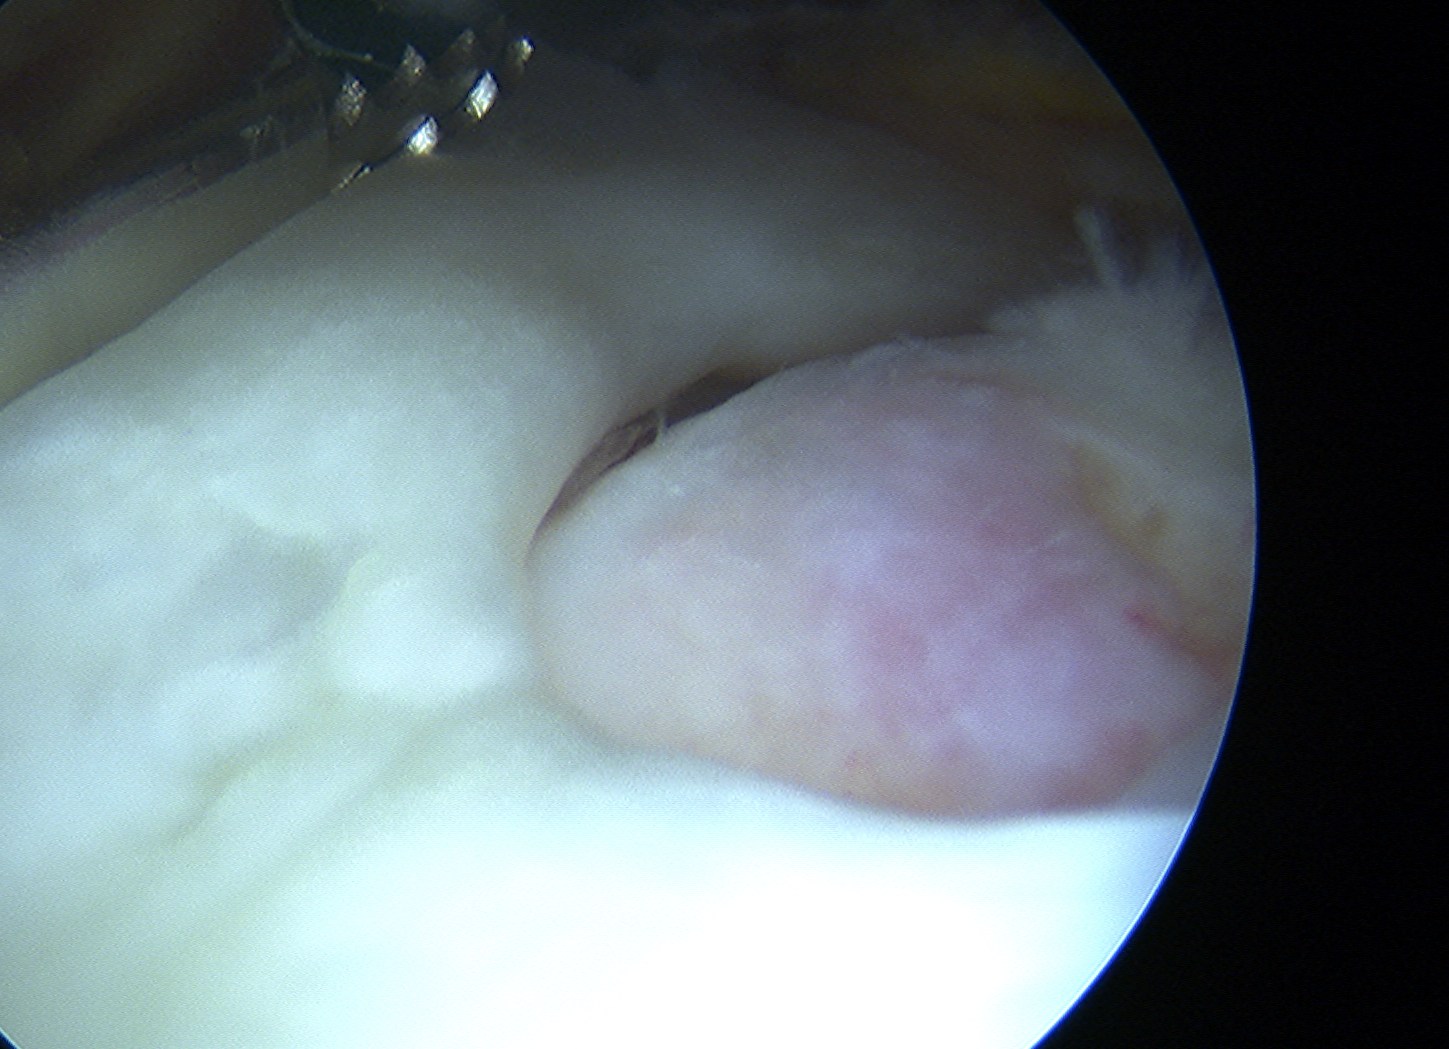

Glenohumeral joint

- inspect subscapularis

- evaluate SLAP / LHB tendinosis - tenotomy / tenodesis

Subacromial joint

- bursectomy for visualization

Arthroscopic Supraspinatous Repair

Technique